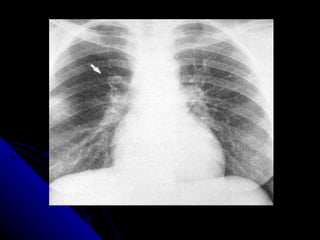

MASA DE MEDIASTINO ANTERIOR TIMOMA

MASA DE MEDIASTINOANTERIOR TIMOMA